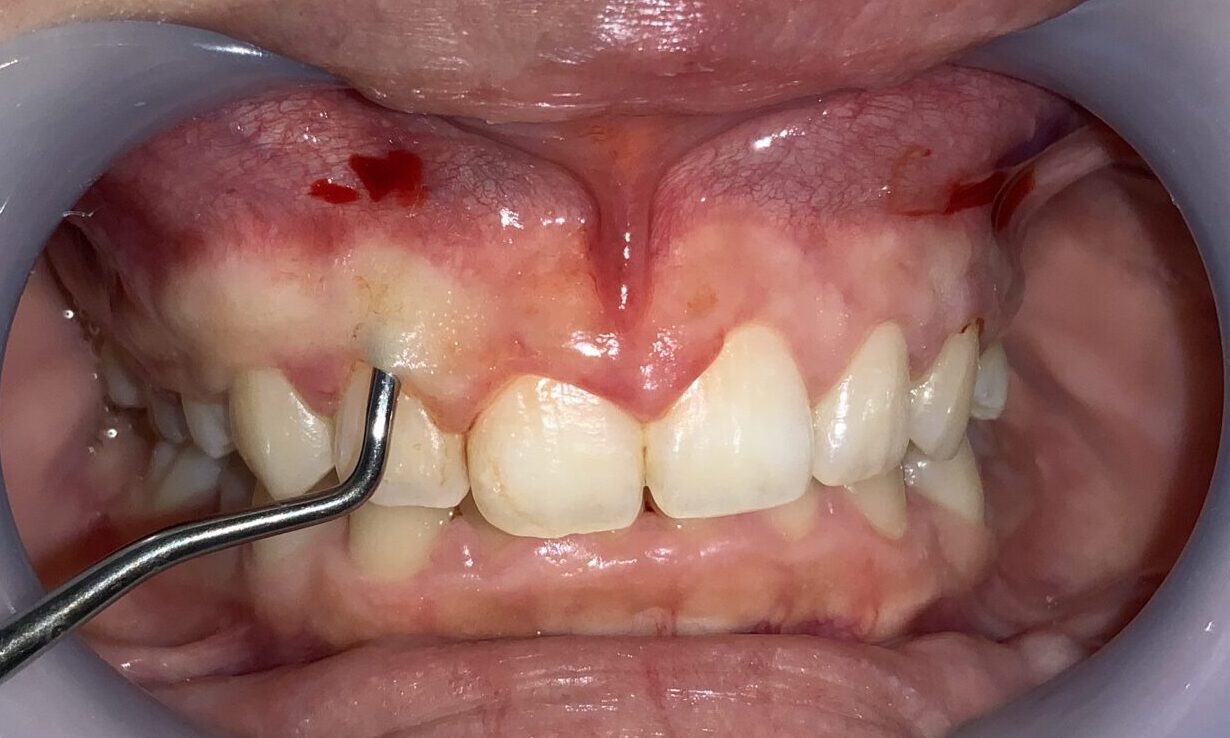

まずは1本だけ歯冠長延長術を行い、切除範囲や歯の大きさ、歯ぐきの長さ、歯と歯ぐきのマッチングを患者様に確認をして頂きます。

1本だけですが、このように違いがわかります。特にこの歯は、歯槽骨がとがっていたので、歯槽骨整形も同時に行いました。追加の費用はありません。

向かって左側(患者様の右側)を全て整えました。

左右の差がはっきりとわかります。

大きく綺麗になりました。

口もとを見てみましょう。

治療の成果がわかるように半分だけの状態で、患者様にもご確認を頂き、大変喜んで頂きました。

歯の形や歯ぐきの形、歯と歯ぐきのマッチング、口もとから見える歯ぐきの状態は完璧です。